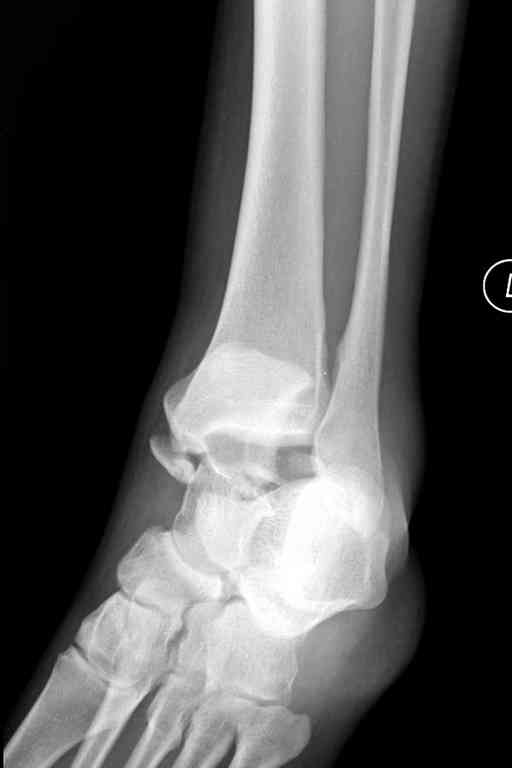

Переломовывих тарана с повреждением медиальной стороны. Через 4 часа после поступления проведена репозиция и фиксация тарана после Irrigation&Debridment. Частичное несращение медиальной лодыжки не беспокоит, вернулся к активному образу жизни. Полная нагрузка разрешена через 11 недель. Финальные снимки через 11 месяцев.